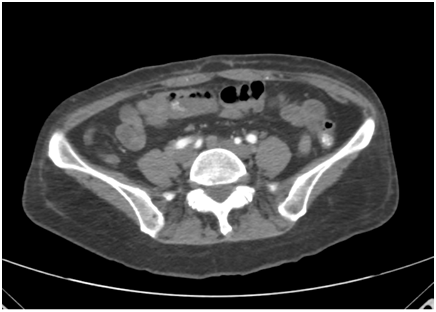

A 60-year-old Asian female with a history of hyperlipidemia and a remote diverticulitis requiring right hemicolectomy presented with diarrhea for 11 weeks. Bowel movements were described as Bristol Scale 6, dark brown, with occasional hematochezia, and without mucous.  Associated symptoms included weakness, several episodes of non-bilious, non-bloody vomitus and a 16-pound weight loss. The patient denied abdominal pain. Family history included gastric carcinoma. On hospital admission, physical examination was unrevealing. Laboratory investigations demonstrated leukopenia to 1.9K/µL, normocytic anemia of 9.1g/dL, thrombocytopenia of 120K/µL, hypoalbuminemia of 2.8g/dL, and elevated erythrocyte sedimentation rate at 50mm/hr. A contrast abdominal computerized tomography (CT) scan failed to reveal gastrointestinal abnormalities (Figure 1).

Lupus enteritis is defined as either vasculitis or inflammation of the small bowel with supporting imaging or biopsy findings. Typical symptoms include abdominal pain, diarrhea, and vomiting. CT scan is often the diagnostic test of choice. Imaging may show evidence of focal or diffuse bowel wall thickening, bowel dilation, abnormal wall enhancement or target sign, enlarged and increased number of mesenteric vessels, and fat stranding (Figure 1).3,6

Figure 1 Abdominal CT scan showing normal small bowel and colon.